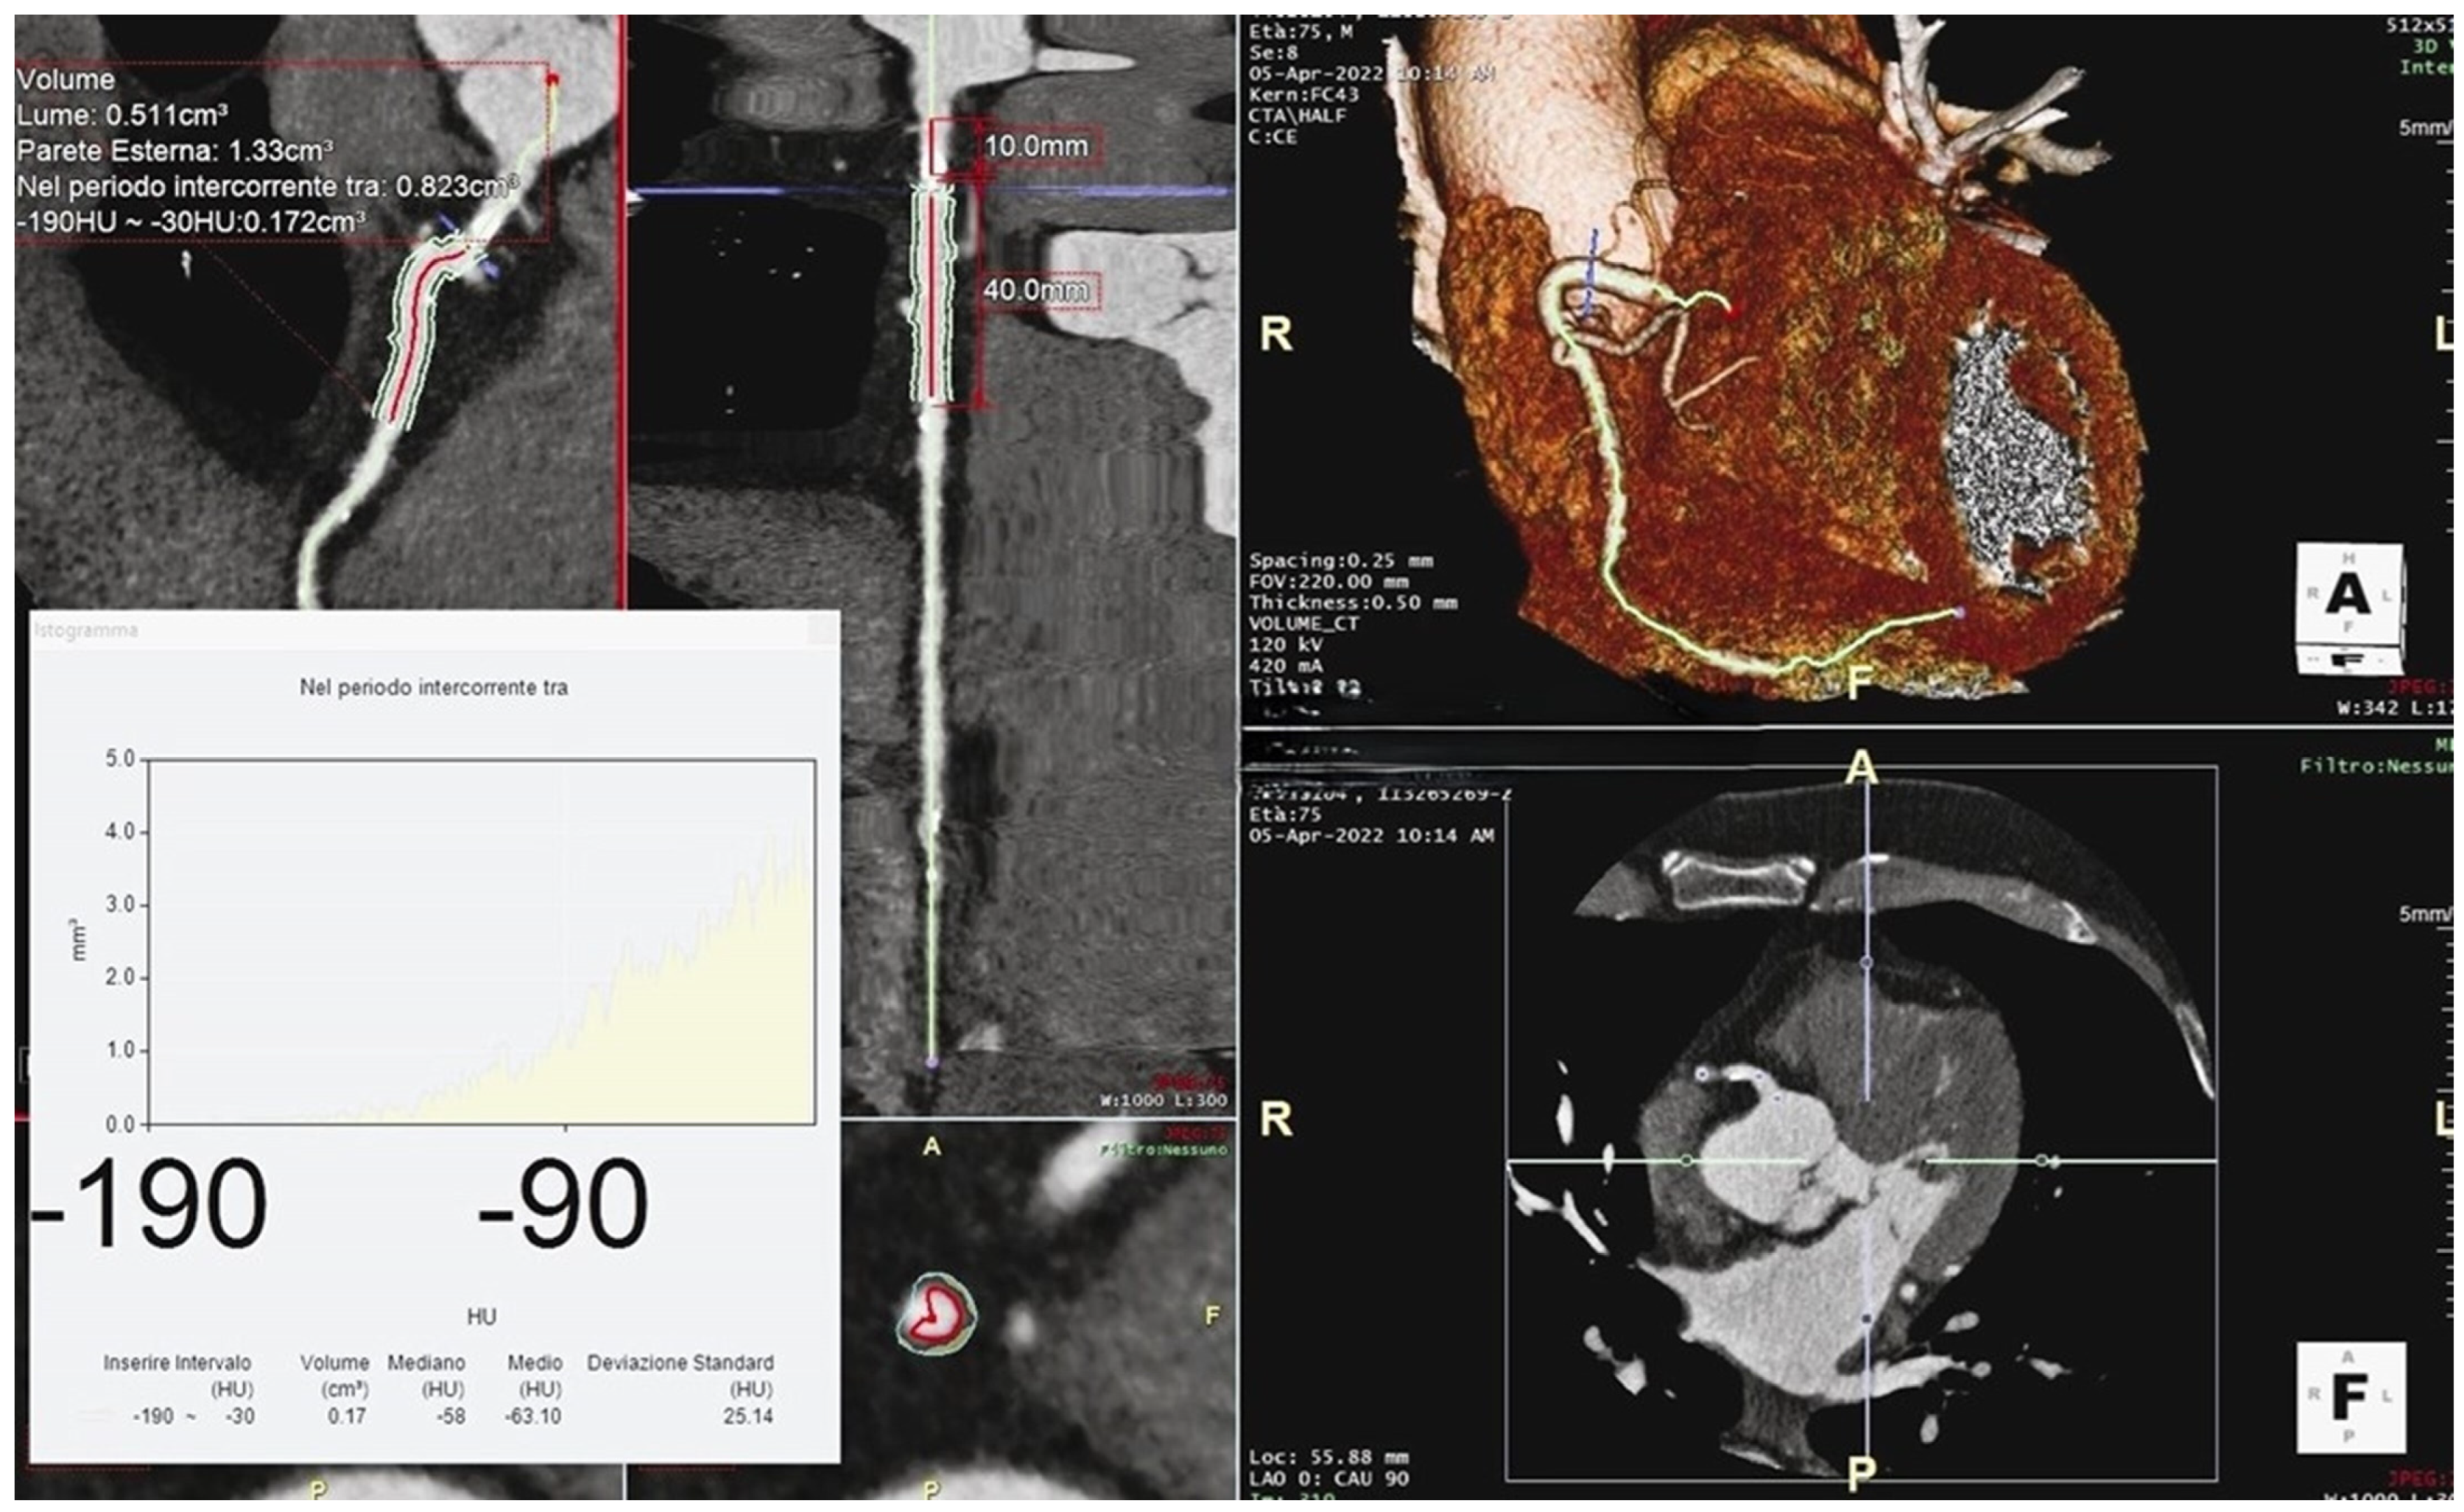

2. Coronary Calcium Score

2.2. Measurement

3. Perivascular Fat Attenuation Index

3.2. Measurement